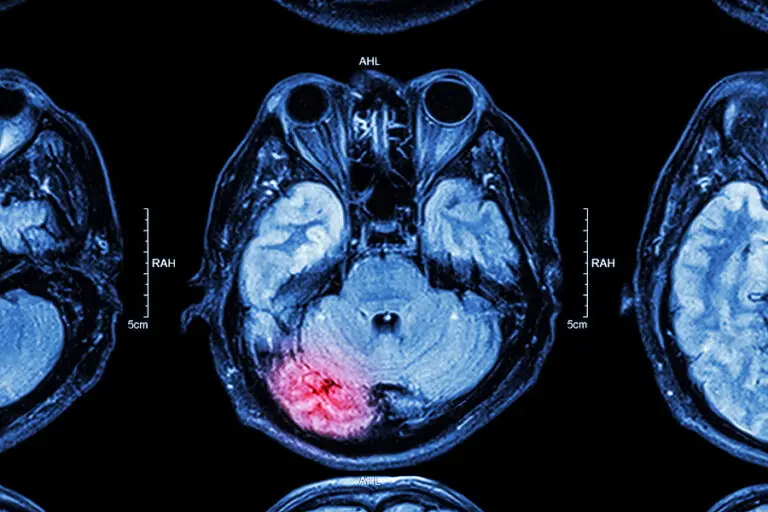

Even relatively mild concussions caused by light bumps to the head could potentially cause long-term problems, according to a recent study. The new data shows that the brain’s wiring can change in the aftermath of

Boston University researchers have discovered the degenerative brain injury called chronic traumatic encephalopathy (CTE) in 345 of 376 former NFL players they have studied. News reports indicate that BU’s CT Center researchers have been raising

In an unprecedented move that will have ramifications for contact sports at all levels, the U.S. National Institutes of Health (NIH) has formally acknowledged that there is a causal link between repeated blows to the